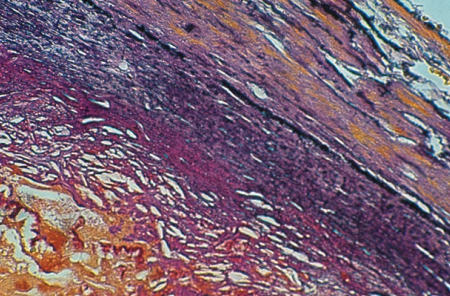

Weigert Van Gieson rapid method 100 test - cat# 04-053812 Bio Optica Special Stains

Product for the preparation of cyto-histological samples for optical microscopy. To show elastic fibres, connective tissue and nuclei at the same time. Recommended for vascular pathology.